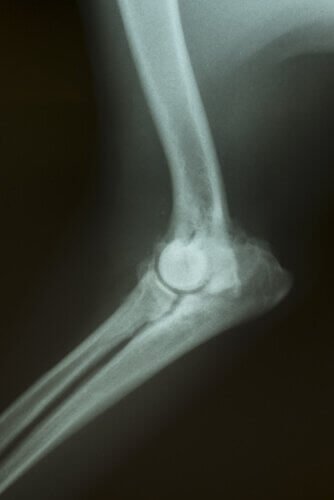

As articulações são uma união entre os ossos do corpo, que se movem graças à cartilagem articular que cobre essas articulações e permite a mobilidade desses ossos para o uso da articulação.

Bem, essa cartilagem envelhece e com o tempo começa a falhar, a perder a lubrificação e a desnutrir-se, com o consequente fato de que a dor começa quando se quer mover as articulações. A doença é degenerativa e não tem cura, mas há muitas coisas que podem ser feitas para atenuar um pouco os sintomas.